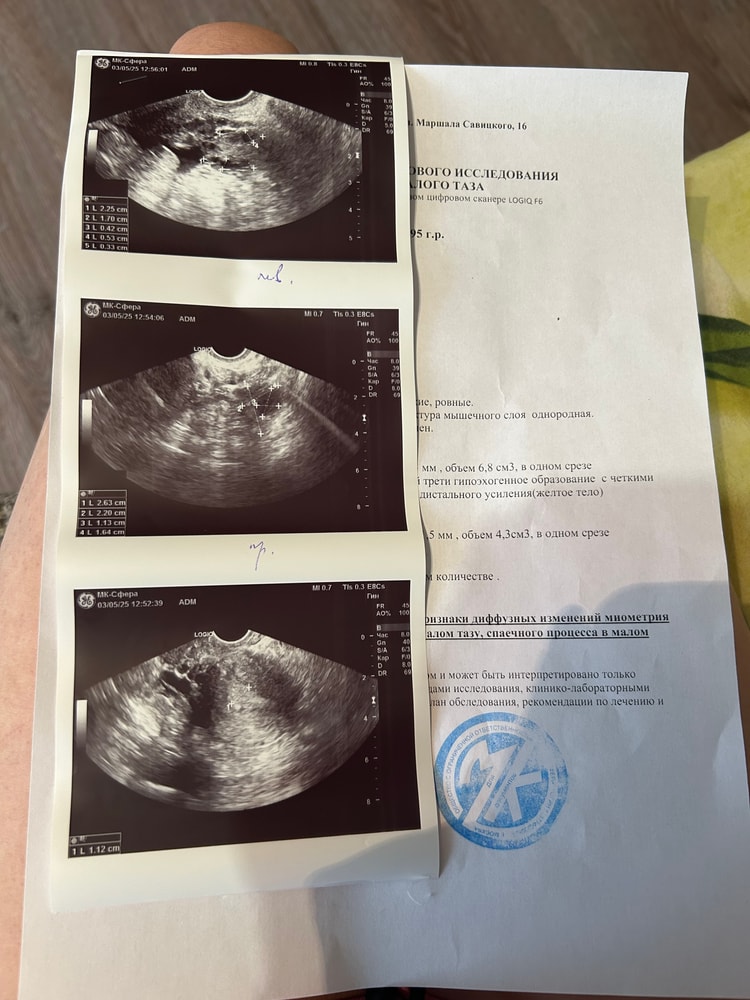

Всем привет ,сказали жидкость позади матки и вокруг левого яичника ,Нужна консультация гинеколога,но овуляция была ,но где же месячные 🩸 может она была недавно